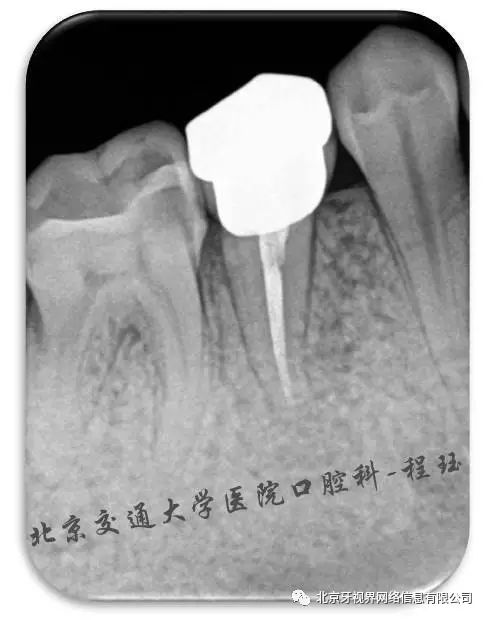

根管治疗片子,根管治疗图片片子

根管治疗伤脑筋的拍片2

记录一例一波三折的根管治疗案例

根管治疗后的牙片,求诊断.